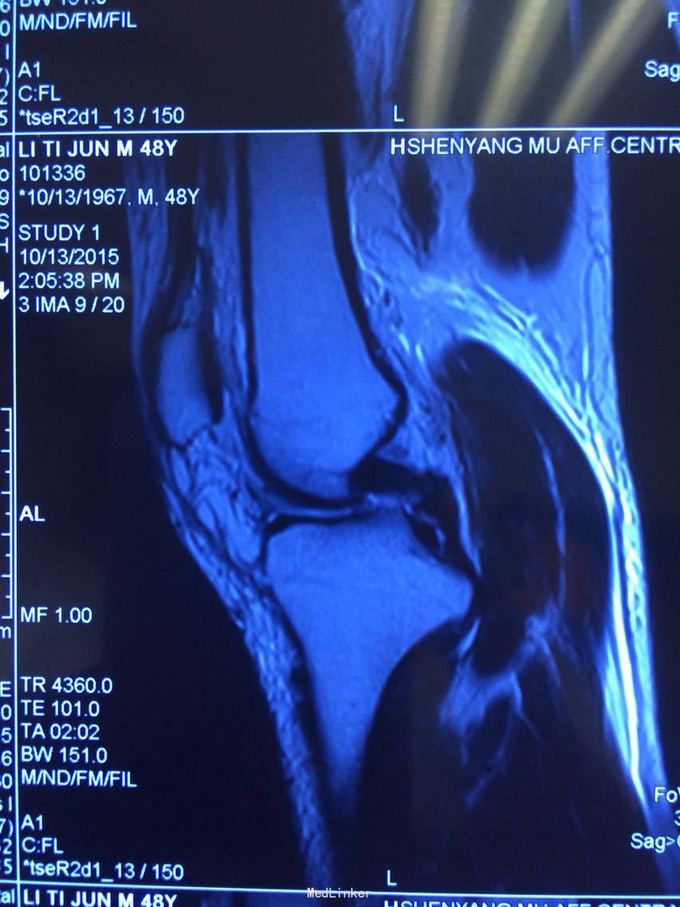

交通伤后膝关节疼痛,关节不稳。 患者交通伤,膝关节肿胀、疼痛,活动受限,肿胀消退后关节不稳。

查体:髌骨稳定,拉赫曼试验阴性,台阶征阳性3+,拨号征阴性,外翻0度阴性、30度阳性,内翻阴性。

诊断:膝关节多发韧带损伤,后交叉韧带、内侧副韧带 处理:给予关节镜下后交叉韧带重建,小切口修补内侧副韧带,取自体半腱股薄肌腱

后交叉韧带和内侧副韧带也有协同作用,后交叉韧带相比前交叉韧带术后容易出现松弛,故内侧副韧带也一期给予修补,后交叉韧带也可以选择inlay方法,但首次重建建议全镜下。